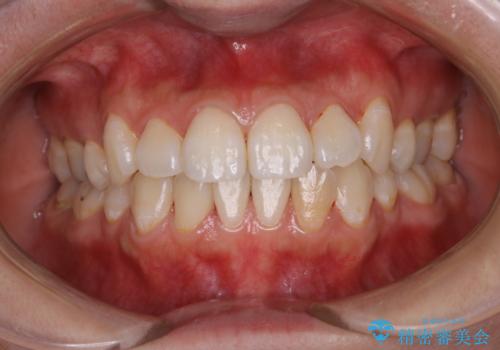

インビザラインでの矯正治療前にPMTCで歯のクリーニング

- 矯正治療の前にクリーニング希望で来院されました。PMTC30分コースを行いました。

PMTCは、国家資格取得者の歯科衛生士により、専門的な機械や材料を使用してのクリーニングです。一人一人の患者様のお口の状態に合わせたクリーニングを行います。

矯正治療は、歯を動かすため歯肉にも負担がかかります。そのため、矯正前にしっかりクリーニングを行い健康なお口の状態にしておくことが大切です。